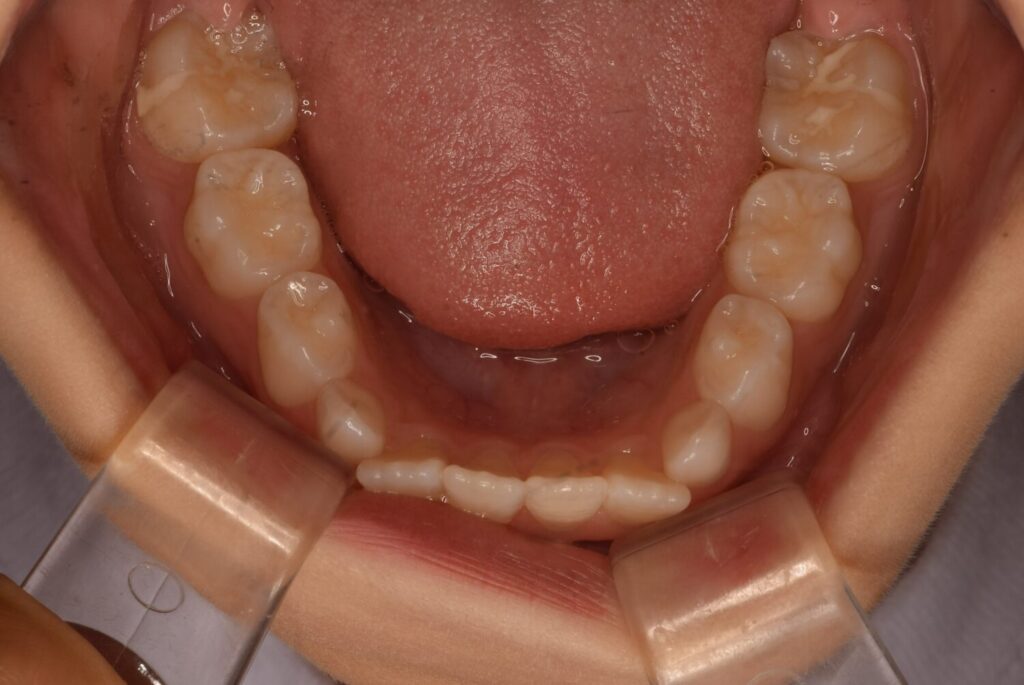

3ヶ月後の変化の写真です。

平坦だったのはなくなり綺麗なアーチになりました。

マウスピースをつけることで飲み込み方の改善や力のかかり方が変わるため変化が起きやすいです。

アクティビティーやマウスピースを行なってくれていると変わります。

次の生え変わりは3番目の歯です。

この歯は根っこが長く、よく八重歯と呼ばれ、外側が出ているような歯になることが多いです。

実際に生えてくるとこのように大きい歯が出てきます。

幅が足りずこのままでは八重歯になってしまいそうでした。